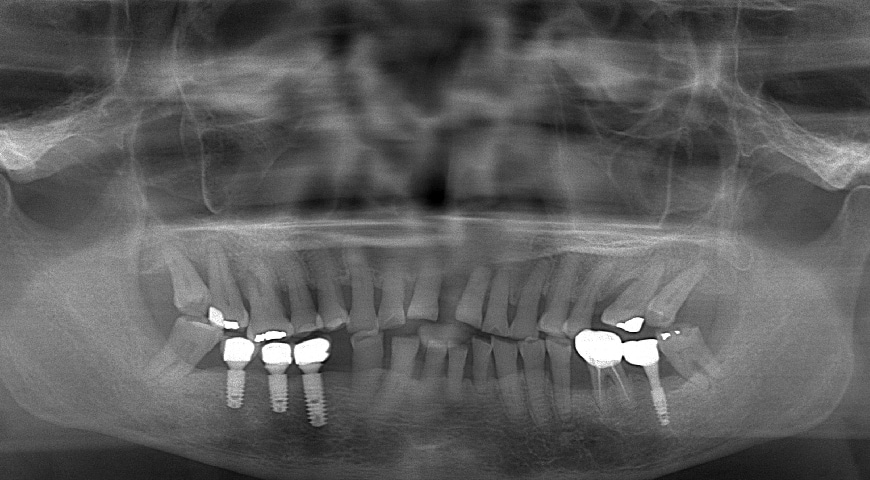

例如這位先生的右下第二小臼齒,在牙周治療前,牙周囊袋的深度有 7 – 8 mm,並且從X光片顯示出有明顯的骨頭缺損。其實就是很有可能需要進入第二階段手術治療的情況。

但僅僅經過了雷射輔助第一階段治療,患者也規律配合改善口腔衛教,後來在追蹤期,我們就發現牙周囊袋已經改善到 2 – 3mm 的正常測量深度值,骨頭的缺損竟然也自然生長癒合!

其實我們很有信心,未來這顆牙齒會因為牙周問題而鬆動的機率非常低,確實後來也保存超過十年!

牙周治療前後,牙齦紅腫的狀況明顯改善

經雷射輔助牙周治療,患齒的牙周囊袋降低至正常的探測深度

治療後,牙周齒槽骨自然再生